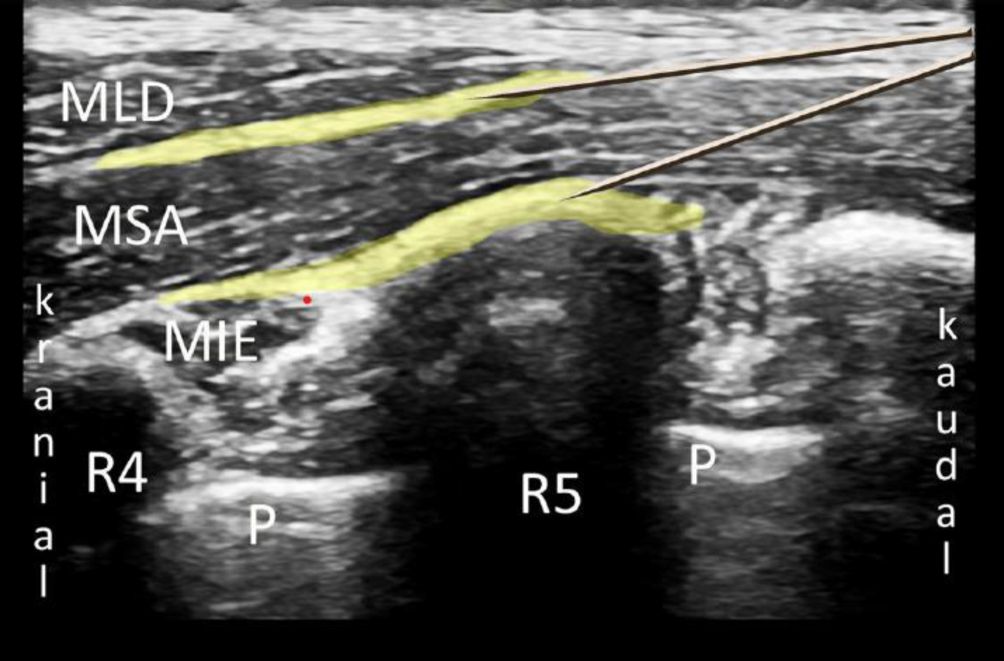

Für die Anlage wird in Rückenlage der Arm der zu infiltrierenden Seite abduziert. Sonographisch wird in der mittleren Axillarlinie in sagittaler Ausrichtung die Faszie des M. serratus anterior dargestellt. In plane kann von medial infiltriert werden (Abb. 5). Es werden ein oberflächlicher und tiefer SAP-Block unterschieden, bei denen das Lokalanästhetikum entweder ober- oder unterhalb des M. serratus anterior eingebracht wird (Abb. 6). Steinfeld et al. empfehlen die Verwendung von 20–40 ml 0,2- bis 0,5 %iger Ropivacainlösung [31]. Es existieren Fallberichte über Rippenfrakturen oder Thorakotomien, in denen eine Laufrate von 7 ml/h unter Verwendung von 0,0625- bis 0,1 %iger Bupivacainlösung angegeben wurde [20, 23].

Abb. 6

Sonographische Darstellung eines Serratus-anterior-plane-Blocks. Oberflächliche Blockade mit Ausbreitung des Lokalanästhetikums (LA) zwischen den Muskelfaszien von MLD und MSA; tiefe Blockade mit Ausbreitung des LA zwischen MIE und MSA. MLD M. latissimus dorsi, MSA M. serratus anterior, MIE M. intercostalis externus, R4 4. Rippe, R5 5. Rippe, P Pleura. LA gelb dargestellt. (Aus Steinfeldt et al. [31])

Durch die Infiltration zwischen die Faszienblätter wird ein Ausschalten des N. intercostobrachialis sowie lateraler Äste der Interkostalnerven erreicht, was in der Regel eine Anästhesie der anterioren Brustwand auf Höhe Th 2–Th 6 sowie der lateralen Brustwand auf Höhe Th 2–Th 8 bewirkt [6].